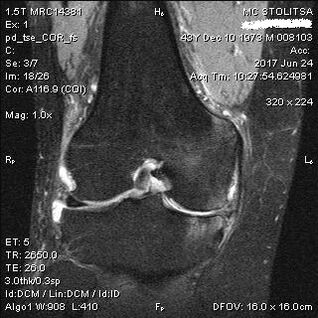

El diagnóstico de osteoartritis de la articulación de la rodilla se realiza en el consultorio de un reumatólogo u ortopedista. El médico examina la articulación afectada, la palpa, escucha las quejas y hace preguntas adicionales. Realiza varias pruebas, por ejemplo, pidiendo al paciente que doble la pierna o dé algunos pasos. Si luego es necesario aclarar el estadio de la enfermedad o la naturaleza de los cambios patológicos, le derivará a más exámenes. Por ejemplo para tomografía computarizada o radiografía.